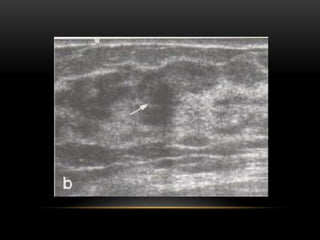

Forma

Ovalada

Redondeada

Irregular

Orientación

Paralela

No paralela

Márgenes

Circunscritos

No circunscritos

Límites de la lesión

Interfase abrupta

Halo ecogénico

Patrón ecogénico

Anecogénico

Hiperecogénico

Complejo

Hipoecogénico

Isoecogénico

Hallazgos acústicos

posteriores

Sin hallazgos

Refuerzo posterior

Sombra acústica

Mixto

Nódulos (ecografía)